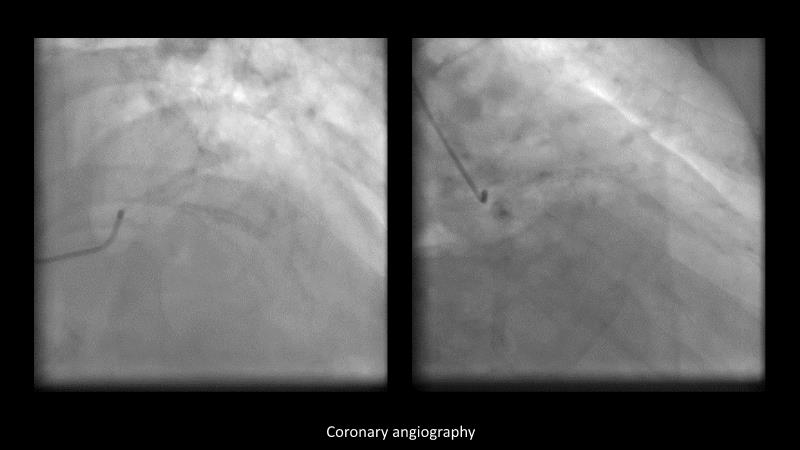

Making treatment and management of complex PCIs easier with Cre8 EVO

Maximize patient clinical outcomes in complex percutaneous coronary interventions (PCIs) by joining this session. Discover how accurate patient evaluation, advanced imaging/functional modalities, optimized procedures, and the Cre8 EVO device contribute to improved safety and efficacy, and review the challenges associated with DES implantation in complex PCIs.

- To find out how an accurate evaluation of patient profile, imaging/functional modalities, optimised interventional procedure and the proper selection of the device contribute to maximise patient clinical outcomes both in terms of safety and efficacy